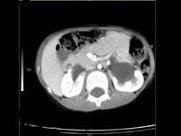

- 多项选择题女,6个月, CT扫描如图所示,下列说法正确的是 ( )

A、双侧肾盂积水

B、双侧肾门朝向前内方

C、双肾下极融合

D、考虑为异位肾

E、考虑为马蹄肾

- 女,6个月, CT扫描如图所示,下列说法